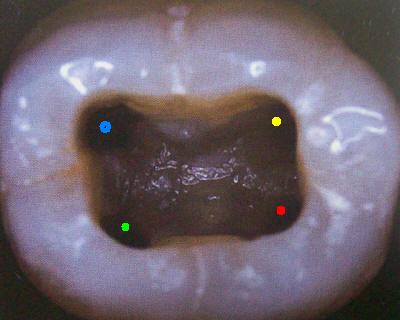

Primer Molar Inferior Esta pieza dentaria es la más voluminosa de la arcada. Posee por general dos raíces bien definidas una mesial y otra distal, ambas aplanadas en sentido mesiodistal. La raíz mesial presenta una curvatura acentuada, mientras que la distal puede ser algo curva o recta. Cuando tiene tres conductos el mas amplio es el distal con una sección oval y su curvatura es suave o recta. Si presenta cuatro conductos la raíz distal contendrá dos de ellos y son de diámetro más pequeño y en caso de presentar dos conductos, ambos son amplios. Segundo Molar Inferior Es de menores proporciones que el primer molar y sus raíces en general son dos y diferenciadas como en el primer molar ,así como también pueden presentarse fusionadas parcial o totalmente. |